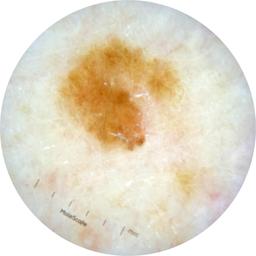

ISIC_6708537

Information

2077 x 2077

Clinical

Field Value

acquisition_day 525

age_approx 70

anatom_site_1 Upper extremity

anatom_site_general upper extremity

concomitant_biopsy False

diagnosis_1 Benign

diagnosis_confirm_type single image expert consensus

family_hx_mm False

fitzpatrick_skin_type I

image_manipulation instrument only

image_type dermoscopic

lesion_id IL_6558300

patient_id IP_3297880

personal_hx_mm True

sex female